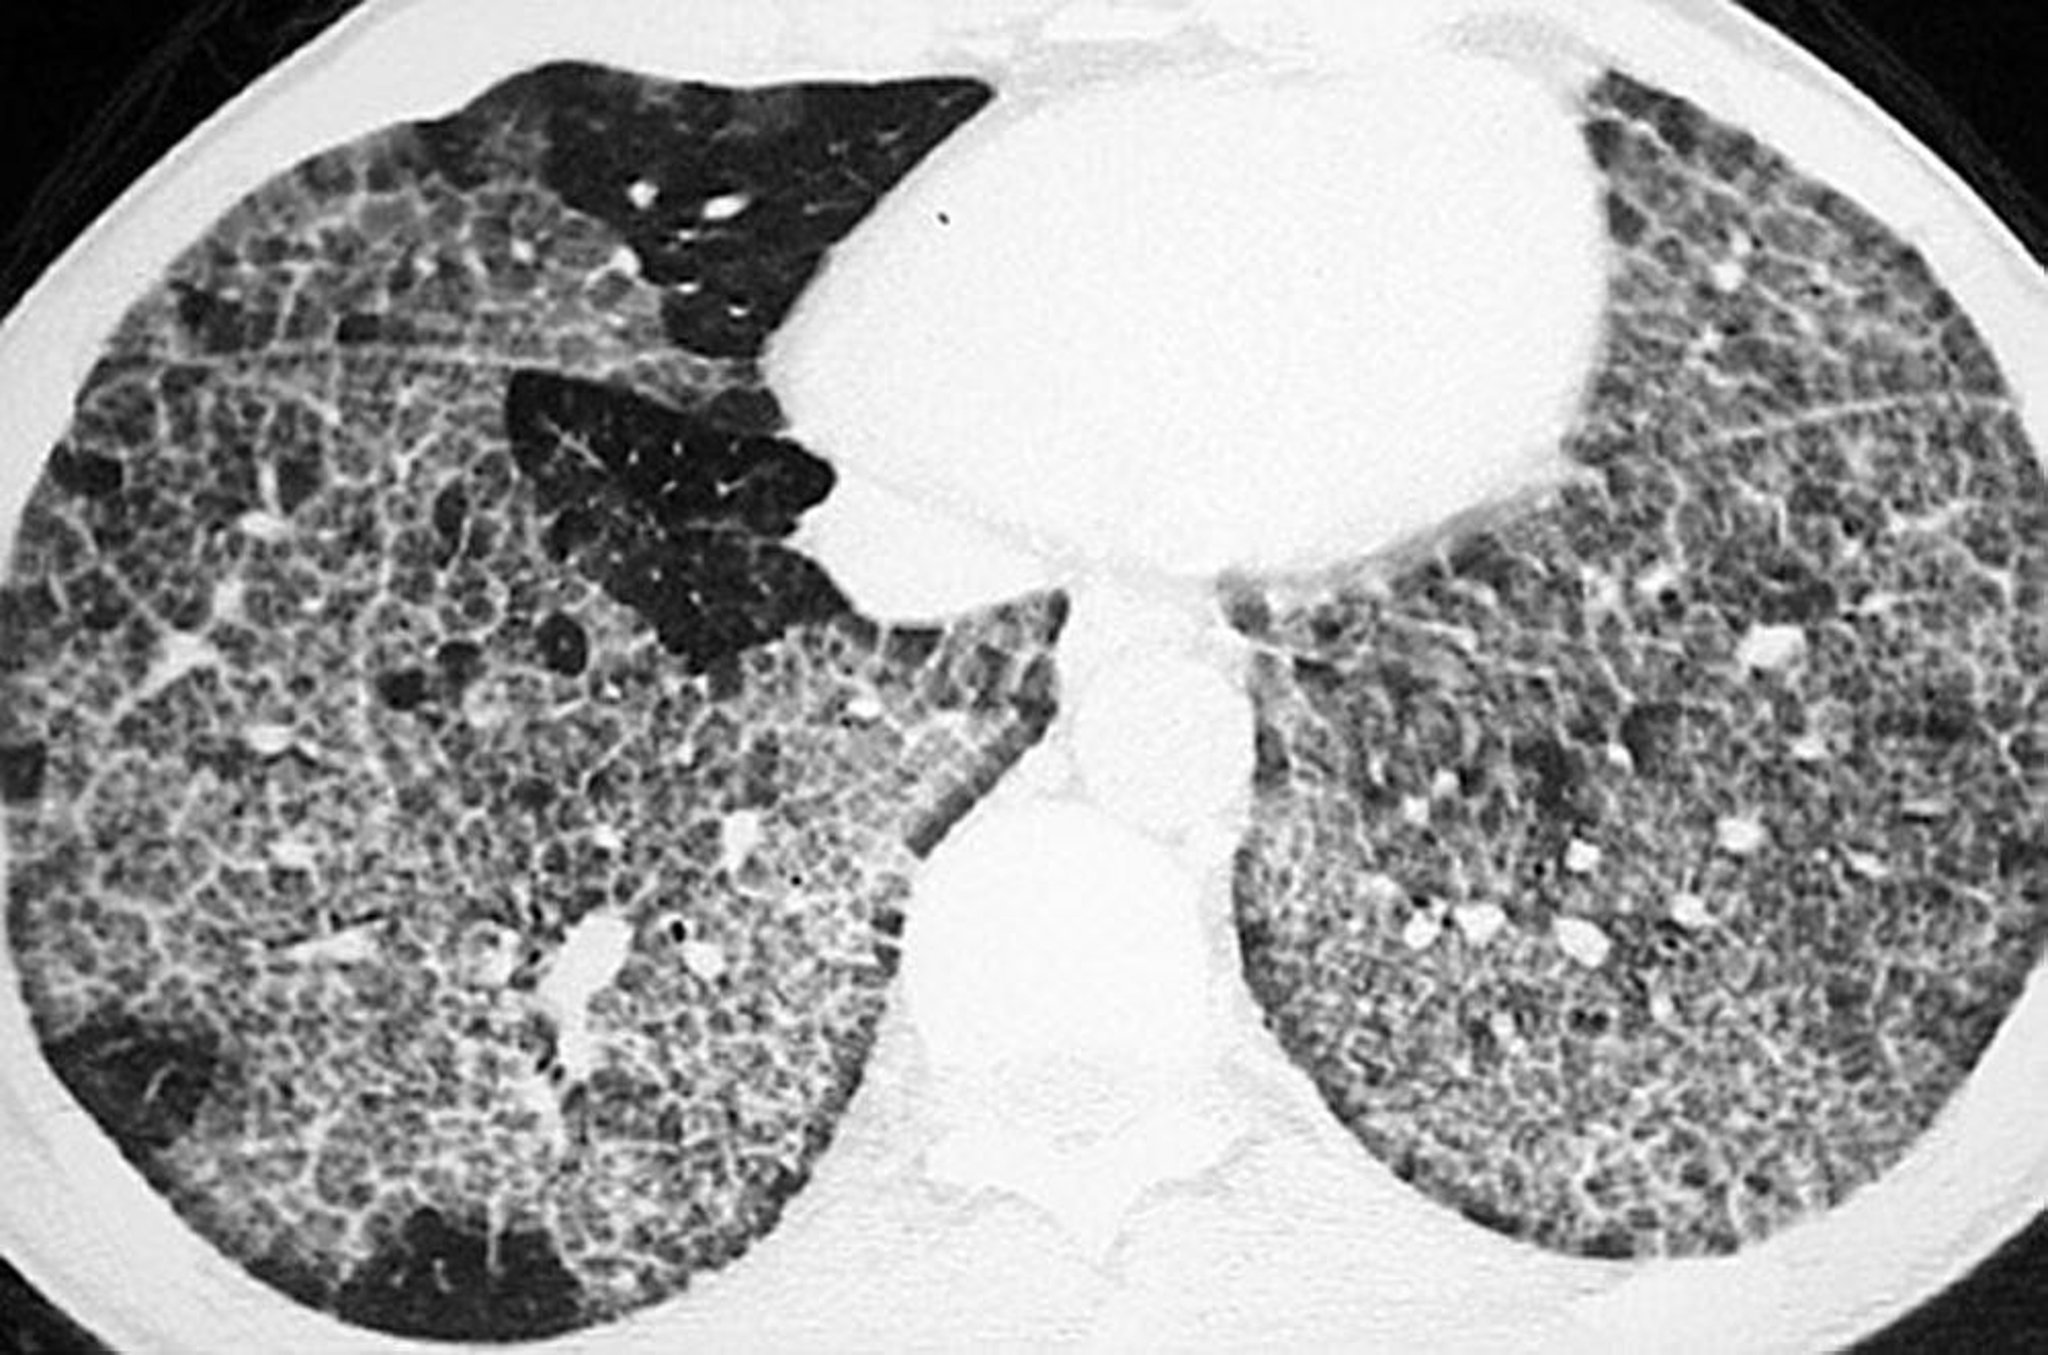

Bệnh tích protein phế nang (chụp CT)

CT độ phân giải cao cho thấy hình ảnh kính mờ, cấu trúc nội thùy dày lên và vách nội thùy tạo hình ảnh đa giác điển hình (“lát gạch”).

Hình ảnh do bác sĩ Talmadge E. King cung cấp